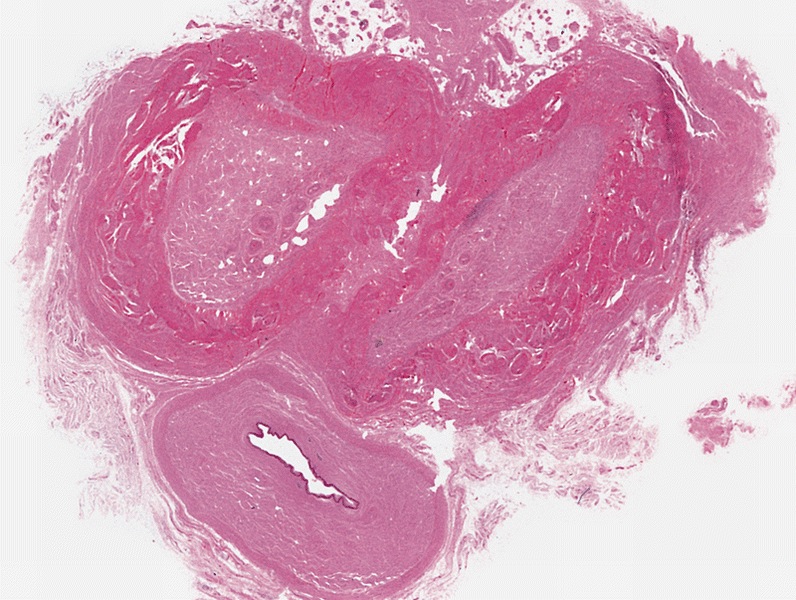

Gross description

- Irregular areas of fibrosis in tunica albuginea with or without nodules in penile shaft

- Occasionally nodular areas of fibrosis may predominate

Microscopic (histologic) description

- Dense fibrous nodules, similar to those in Dupuytren contracture, fibromatosis and other desmoplastic conditions involving myofibroblasts

- More dense and less cellular than other types of superficial fibromatosis

- Disorganization of collagen of tunica albuginea with formation of nodules, often hyalinizing fibrosis

- Perivascular lymphoid infiltrate in early stages of disease in 1/3

- Fibrotic tunica albuginea with extension of fibrosis to corpus cavernosum

- Abnormal vessels with venous leakages

- Calcification or ossification may occur, linear band of calcification in 1/4 (J Urol 1997;157:282)